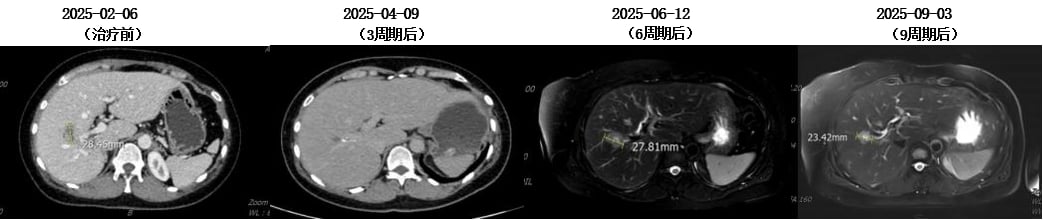

6. 第五次复发与新一代ADC药物的突破(2025至今)

2025年2月,患者再次出现疾病进展,头颅MR显示左侧额顶叶异常强化软组织肿物,伴周围脑组织水肿,考虑脑转移。胸腹部CT显示肝脏病灶增大。

面对脑转移的再次出现,MDT团队决定启用新一代ADC药物——T-DXd(德曲妥珠单抗)。德曲妥珠单抗是目前HER2阳性乳腺癌治疗领域的一颗“新星”,它具有更高的药物抗体比(DAR),即每个抗体携带更多的化疗药物分子,同时具有“旁观者效应”,可以杀死周围未表达HER2的癌细胞。这使得它在治疗HER2低表达和脑转移方面展现出卓越的疗效。

患者接受了11周期的德曲妥珠单抗治疗。仅仅2周期后,患者右下肢无力症状明显好转;4周期后,右下肢肌力恢复,ECOG评分达到0分(意味着完全正常活动)。治疗过程中,骨髓抑制I-II度,胃肠道反应I度,未见间质性肺炎等严重副作用。影像学复查显示,疗效评价为部分缓解(PR)。这再次证明了创新药物在多线治疗失败后,仍能为患者带来显著的生存获益和生活质量改善。